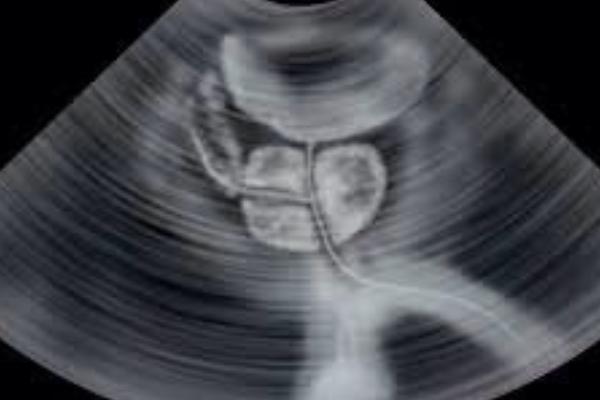

Ultrazvučni pregled prostate može da se obavi na dva načina. Prvi se obavlja transabdominalnom sondom, pri čemu pacijent leži na leđima, a pregled se vrši preko donjeg dijela trbuha. Drugi način je sa tankom transrektalnom sondom kojom se ulazi nekoliko centimetara u završni dio debelog crijeva i prislanja se direktno na prostatu. Ovaj drugi vid ultrazvučnog pregleda prostate …